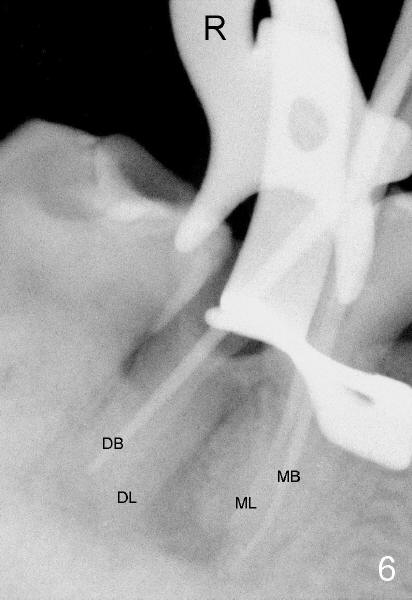

On the second appointment, the buccal wall is fractured (Fig.5: B). Visibility improves. Straight access is obtained, particularly mesially, but DL orifice is still not found. So D canal appears to be the only canal distally. It is further debrided with 40/.04 file. PA is taken when master cones are inserted (Fig.6). This time DL root is quite obvious.

To further improve visibility, the arm of rubber dam clamp is changed from distal to mesial aspect of #30 (compare R in Fig.6 and 7). DL orifice is finally found, close to DB one. The DL canal is obliterated. It is debrided until #20 hand file short of WL. Fig.7 shows the chamber after RCT with gutta percha. * indicates thin pulpal floor. Fig.8 and 9 are taken after build-up (B). It appears that distal canals are divergent apically and that there are most likely two distal roots.